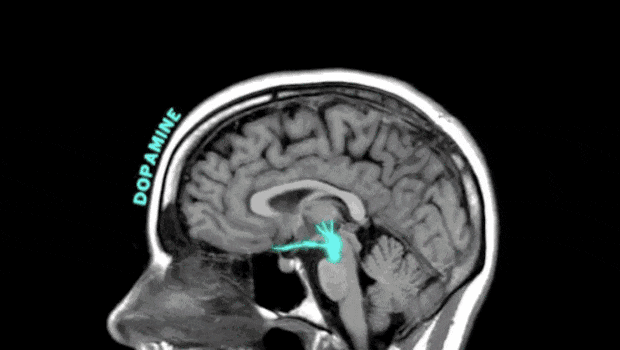

冬天宅在家,一方面减少了人们晒太阳的时间,另一方面户外活动时间也被压缩了。长期缺乏运动会影响神经递质的分泌,如多巴胺、血清素等,这些物质与情绪调节密切相关。周末不妨在暖和的午后逛逛公园或快步走,有助提升大脑内啡肽浓度,让心情变好。天气不好的话,尽量多待在灯光明亮的房间,也能起到类似光照的效果。虽然冬季提倡“早睡晚起”,但如果过度睡眠,会扰乱人体生物钟,使大脑和身体处于慵懒状态,让人感到烦躁、沮丧。为了抵御严寒,人们会有意识地“贴膘”,更倾向于吃高热量、高脂肪食物,如火锅、烤肉等,忽略了蔬果等富含维生素、膳食纤维食物的摄入。不均衡的饮食结构可能影响大脑正常功能与神经递质合成,让人心情变差。

过度摄入高糖和高脂肪食物还可能导致体重增加,影响身体形象和自信心,进一步加重负面情绪。激素是由体内不同腺体生成的化学物质,它的重要功能之一就是调节情绪。以下几种激素能促进大脑的积极感,让人感到快乐和幸福。它是大脑奖励系统的重要部分,与愉悦感觉有关,还参与到人体日常的学习、记忆、运动系统功能之中。多巴胺由酪氨酸合成,豆类、深海鱼类、奶制品和坚果富含酪氨酸,建议适当增加摄入量;新鲜蔬果,尤其是深绿色蔬菜、维生素C含量高的水果等,也有助合成多巴胺。此外,看喜剧、听音乐、运动以及睡眠充足都会增加多巴胺。